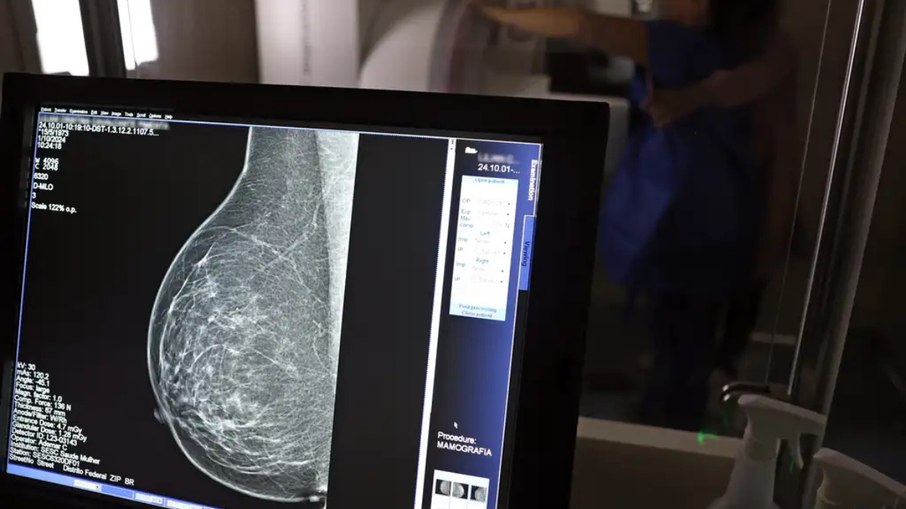

Mulheres entre 40 e 49 anos agora podem fazer mamografia pelo Sistema Único de Saúde (SUS) mesmo sem apresentar sinais de câncer de mama. A novidade foi anunciada pelo Ministério da Saúde na terça-feira (23).

Anteriormente o exame era recomendado para mulheres entre 50 e 69 anos e agora se estende para 40 a 74 anos.

Com a nova regra, a mamografia para mulheres de 40 a 49 anos pode ser feita quando houver necessidade, após a paciente e o profissional de saúde decidirem juntos.

O Ministério da Saúde explicou que, antes, mulheres nessa faixa etária tinham dificuldade para fazer o exame pelo SUS, pois precisavam ter histórico familiar ou sintomas. Mesmo assim, em 2024, mais de 1 milhão de mamografias foram realizadas em pacientes com menos de 50 anos, o que corresponde a 30% do total de exames feitos pelo SUS.